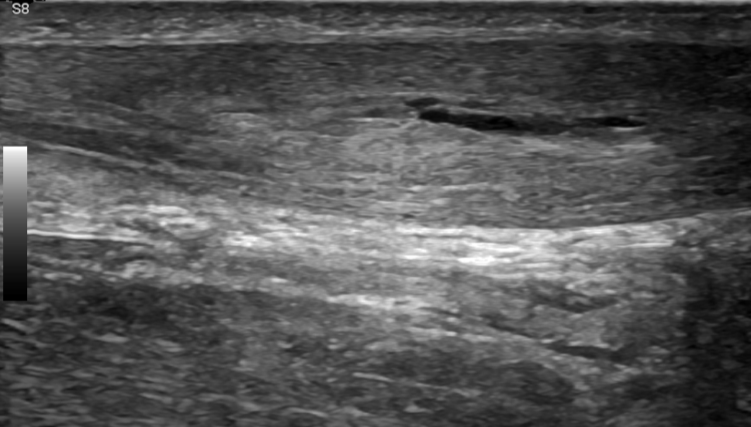

3. Achilles tendon interstitial tear